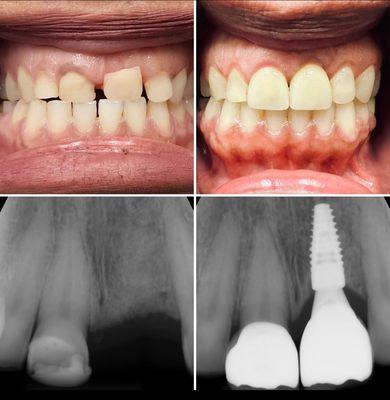

Sol Dental Lab is a professional dental laboratory based in Miami, FL, specializing in creating custom dental prosthetics and restorations for dental professionals.

With a team of skilled technicians and state-of-the-art equipment, Sol Dental Lab focuses on delivering high-quality, precise, and reliable dental solutions to meet the needs of its clients.